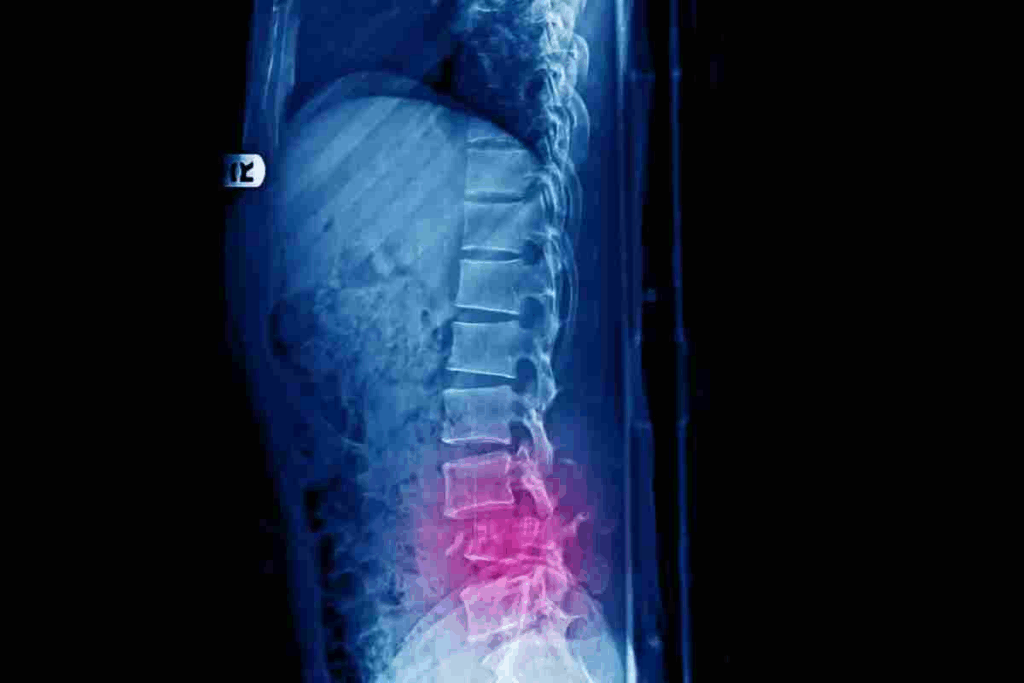

Doctors use a few ways to find vertebral fractures. X-rays are usually the first step. But, MRI or CT scans might be needed for a closer look.

It’s important to know how bad the fracture is. This helps decide the best treatment. Doctors look at how much the bone is collapsed and if nerves are affected.